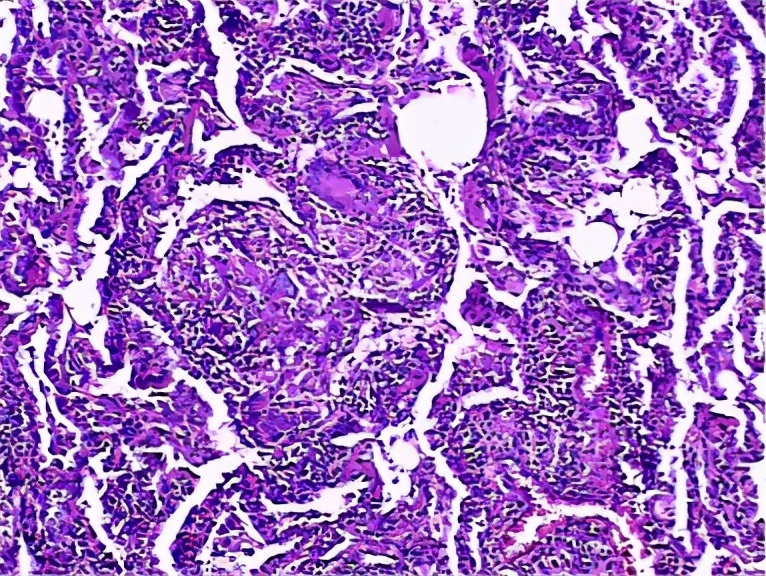

之后进行病理检查:肉芽肿,纤维化,细支气管炎,病理结果符合过敏性肺炎的表现,但是还没有问出病史。

ZYM:肉芽肿,NSIP-like,细支气管炎亚急性表现细胞性NSIP、细支气管炎和肉芽肿三联征,出现<75%。

急性HP:急性纤维素性机化性肺炎。

CLX:慢性HP,纤维化比较明显,肺结构也被破坏,肉芽肿,UIP-lilke,细支气管炎。

慢性HP:气道中心性肺纤维化较明显。

过敏性肺炎实际上是吸入抗原诱发的肺脏免疫炎性疾病,临床表现急、亚急性和慢性过程,以亚急性和慢性多见。目前倾向于按是否有纤维化进行分型,非纤维化型HP多指急性/亚急性,HRCT主要是小叶中心结节、斑片磨玻璃影、马赛克征。纤维化型多指慢性HP,HRCT还可见小叶间隔增厚,不规则粗、细网格,伴牵拉支扩,蜂窝等。病理特点为细支气管炎、不同类型不同程度的间质性肺炎(NSIP、OP、UIP)、肉芽肿。BALF:淋巴细胞增多,>40%。诊断主要是依据抗原及与疾病关系、HRCT、BAL-Lym↑。治疗为脱离抗原,酌情激素治疗。过敏性肺炎是一种可防可治的ILD,所以我们要提高认识,积极防诊治,改善病人生活质量。